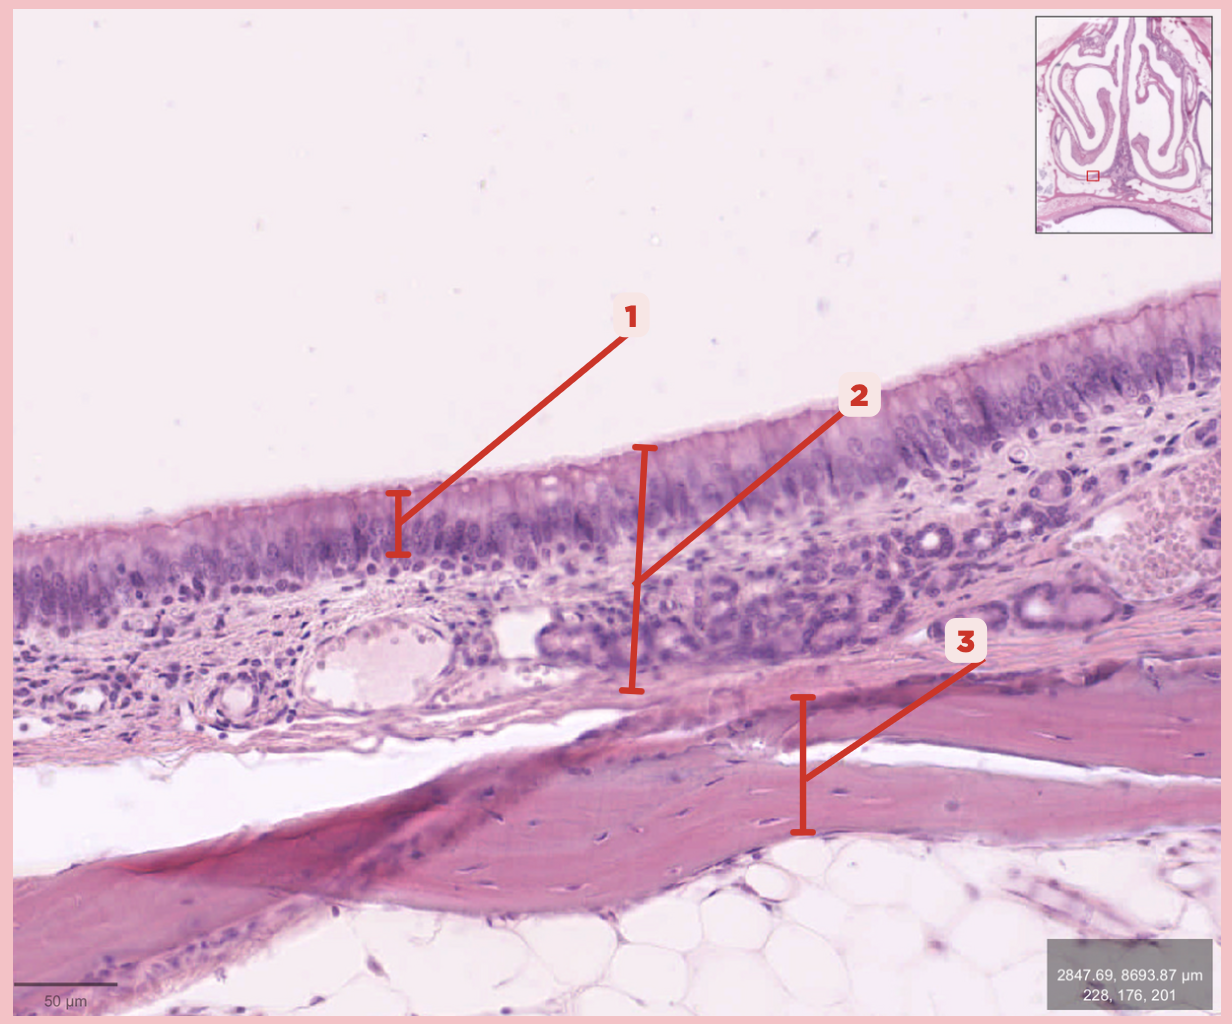

Respiratory Epithelium

Identify the structure labeled as 1.

Mucosa

Identify the structure labeled as 2.

Bone

Identify the structure labeled as 3.

Keratinized stratified squamous epithelium

What’s the lining epithelium at #3?

No

Are Glands present at #1?

Lamina Propria

Identify the structure labeled as 1.

Adipocytes

Identify the structure labeled as 2.

Keratinized stratified squamous epithelium

Identify the structure labeled as 3.